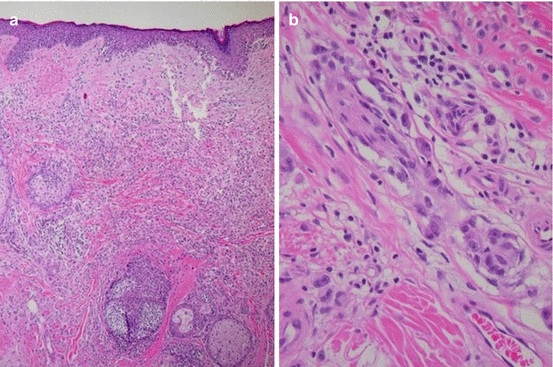

Fig. 17.4

(a) Melanoma Breslow thickness 2.2 mm extending to reticular dermis (H&E, 4×); (b) melanoma invading a nerve (H&E, 40×)

Based on biopsy pathology information, an initial diagnosis of a thin melanoma was made. No further lab or imaging work was performed according to guidelines for an otherwise asymptomatic patient with pT1a melanoma [1]. An excision with 1 cm margins to the deep subcutaneous plane was performed using our staged excision with radial sectioning technique and tissue was sent for 24-hour rush paraffin-embedded permanent sections (Fig. 17.3). The tumor debulking centrally showed residual melanoma with invasion to 2.2 mm Breslow depth, Clark IV, non-ulcerated, mitotic rate 1/mm2, with no lymphovascular invasion, and no satellites (Fig. 17.4a). Perineural involvement was noted at the base of the tumor (Fig. 17.4b). The peripheral margins were clear in all four quadrants.